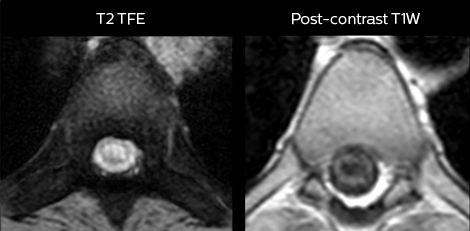

To minimize the time taken to perform scans, rapid MRI examination protocols (ExamCards) were developed, shortening the total scanning time to even less than 10 minutes in some exams. Techniques like mDIXON (modified DIXON) are used for robust capturing of fat-free MRI images in a hectic ED environment.

in image acquisition and postprocessing algorithms.”“mDIXON TSE sequences allow simultaneous characterization of morphological changes from the in-phase T2-weighted images and visualization of edematous changes, thanks to the water T2-weighted images from the same acquisition. Anatomical and morphological considerations could be a partial or complete ligament tear, a bony avulsion or hematoma.”

“mDIXON TSE sequences allow simultaneous characterization of morphological changes from the in-phase T2-weighted images and visualization of edematous changes, thanks to the water T2-weighted images from the same acquisition. Anatomical and morphological considerations could be a partial or complete ligament tear, a bony avulsion or hematoma.”

“mDIXON is robust with regard to susceptibility type of problems that would come up with traditional spectral fat-saturated images.”

“We use mDIXON TSE extensively in our spine imaging in the emergency room,” says Dr. Karis. “It’s particularly nice in that it is very robust with regard to susceptibility type of problems that would come up with traditional spectral fat-saturated images; these problems are essentially eliminated with the mDIXON technique. In our ED environment it’s really nice to have the fat-free imaging that goes along with the mDIXON technique.